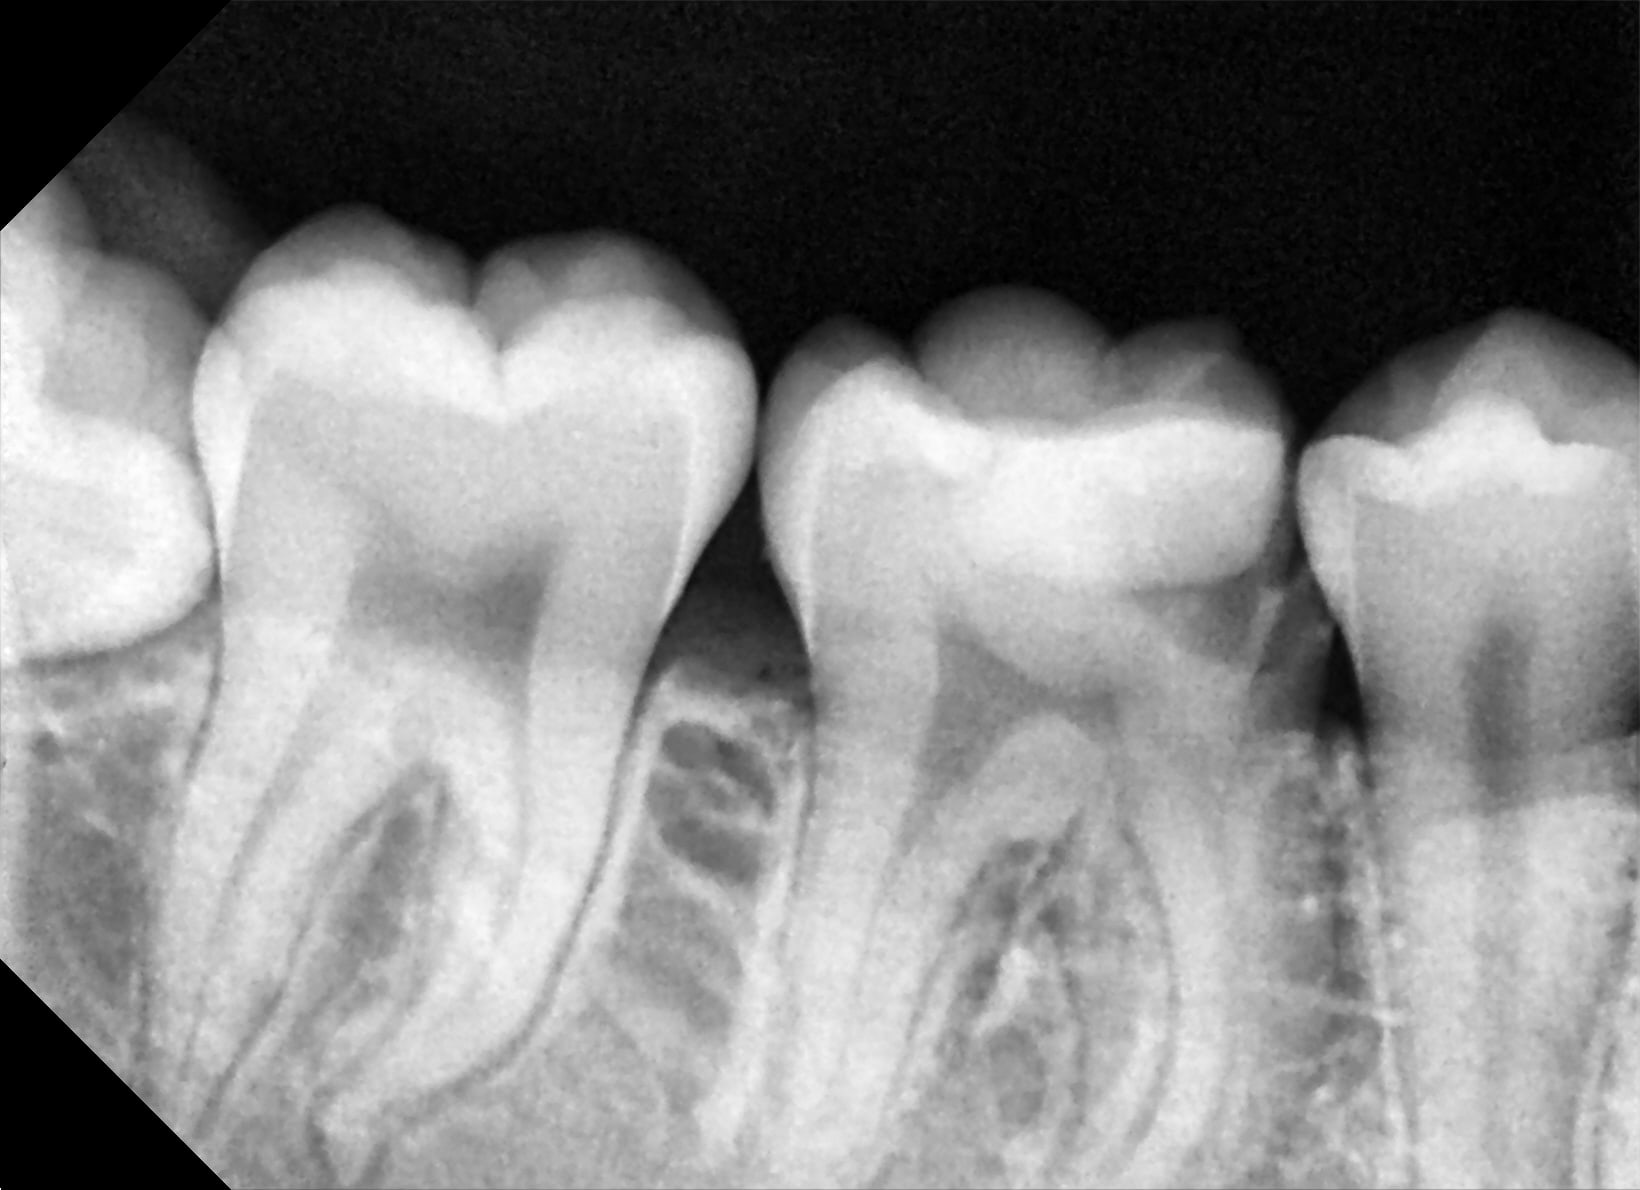

48 cariée jusqu'à la pulpe avec des racines totalement édifiée. Absence de l'ensemble des autres 8. Début de rhyzalise sur la 47.

Vu les reprises de soins sur les dents traitées, tu faits de gros cvi sur les dents soignées en espérant que cela tienne. Il y a peut-être 3endos à gauche si on suit ta pano.

Pourquoi extraire la 47. Oui, il y a nécrose de 22, je ne dis à aucun moment de l'extraire. Tu as des endos sur 22, 23, 25 et 35 à faire. Si il est très à risque de carie, pourquoi parles tu alors de une à deux couronnes. Sachant que tu risque d'avoir autant d'endos de l'autre coté.